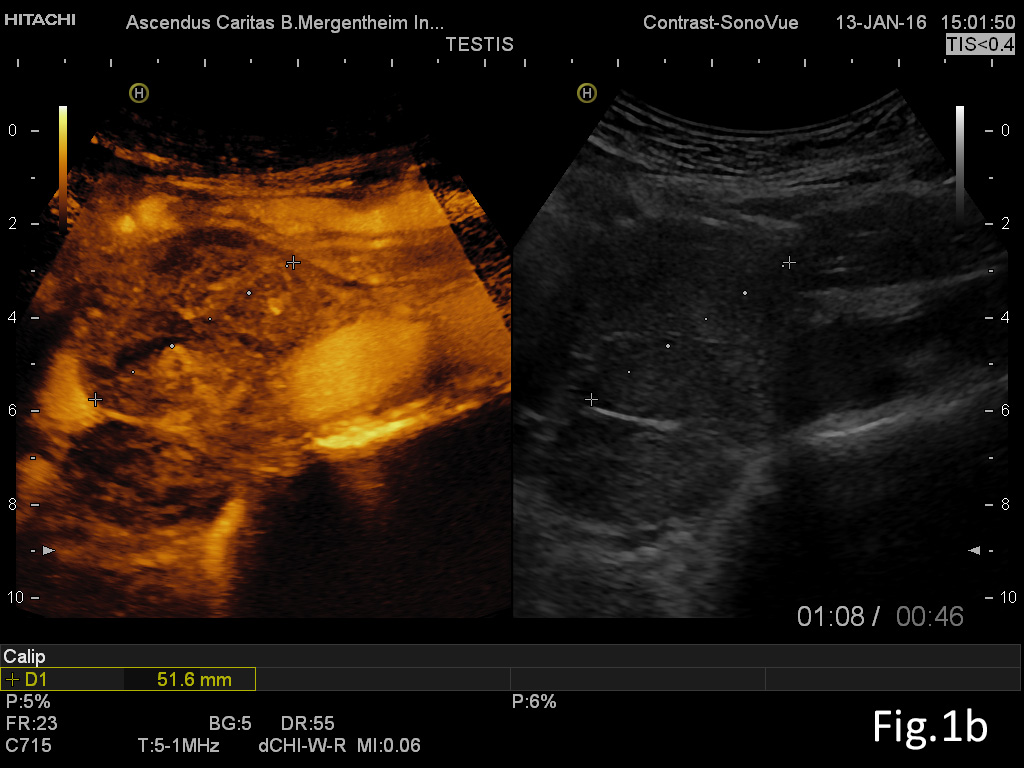

Figure 2: Focal liver lesion using B-mode (a) and contrast enhanced ultrasound (CEUS) in the arterial (b), late phase (c) and CEUS using time intensity curve analysis (TICA) (d). The B-mode ultrasound showed an isoechoic lesion with transducer distal shadowing, somewhat unspectacular. CEUS showed early and slightly hyperenhancing features in the arterial phase and pronounced wash out in the portal venous and late phases indicating metastases and excluding hemangioma [(1)]. The TICA image on the right side of the screen differentiates the initially hyperenhancing lesion (red line) in comparison to the surrounding liver parenchyma (yellow line). In the portal venous phase the red line crosses downward in comparison to the liver parenchyma (yellow line), indicating metastasis [(2-5)].